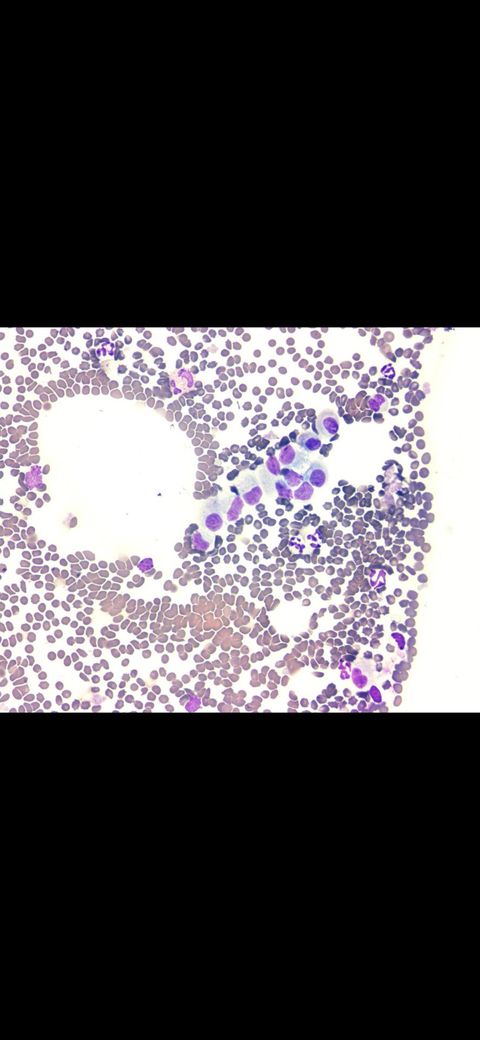

첨부된 사진에 다양한 양상의 비정형의 유사분열상이 관찰되고 핵 대소부동증을 비롯한 악성도를 높게둘 증거들이 관찰되고있습니다.

주치의가 항암을 권했다면 제공된 사진 이외에도 다른 악성지표들이 많이 있을 가능성이 있으니 주치의 의견을 따르시는걸 추천합니다.